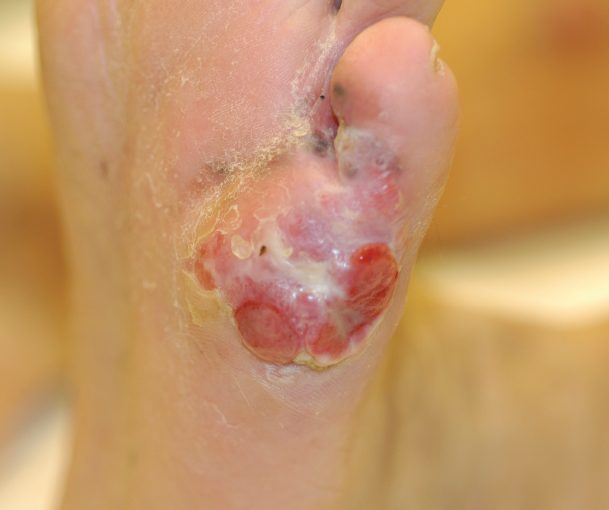

What do you suspect is the cause of the ulcer?

A 57-year-old white male with a history of diabetes and hypertension presents with a 3-month ulcer on his left, plantar foot. The enlarging ulcer, associated with sporadic pain, sent the patient to a vascular surgeon—who preformed an extensive work up that included x-rays, arterial, and venous dopplers. All studies were found to be unremarkable.

Answer: Malignant Ulcer

The result of a skin biopsy confirmed a clinical suspicion that the plantar lesion was an ulcerated, acral lentiginous melanoma. Unfortunately, the melanoma metastasized to the patient’s liver, pancreas, lungs, and thalamus. The patient died within 2 years of the diagnosis. Early detection and excision would have prevented the metastasis.

Typically, venous stasis ulcers occur in the gaiter area—most commonly at medial malleolus and rarely form on the plantar foot. Arterial (ischemic) ulcers usually occur on the distal leg or on the dorsum of foot or toes and do not typically form on the plantar foot. While neurotrophic (diabetic) ulcers can occur on the plantar foot, these ulcers are not painful.

When foot ulcers fail to heal or do not fit typical clinical presentations as described above, a skin biopsy is needed to rule out malignancy. A number of cancers including squamous cell carcinoma, lymphoma and melanoma can present with ulceration on the foot.